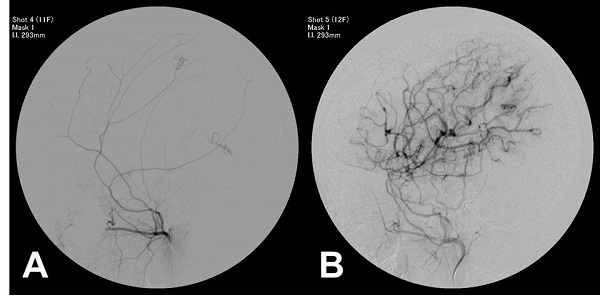

모야모야병의 진단은 주로 뇌혈관 조영술, MRI, CT 스캔 등을 통해 이루어집니다. 이러한 검사들은 뇌혈관의 상태를 확인하고, 혈류의 변화를 관찰하는 데 도움을 줍니다. 특히, 뇌혈관 조영술은 혈관의 구조적 변화를 직접적으로 확인할 수 있는 방법으로, 모야모야병 진단에 있어 중요한 역할을 합니다.